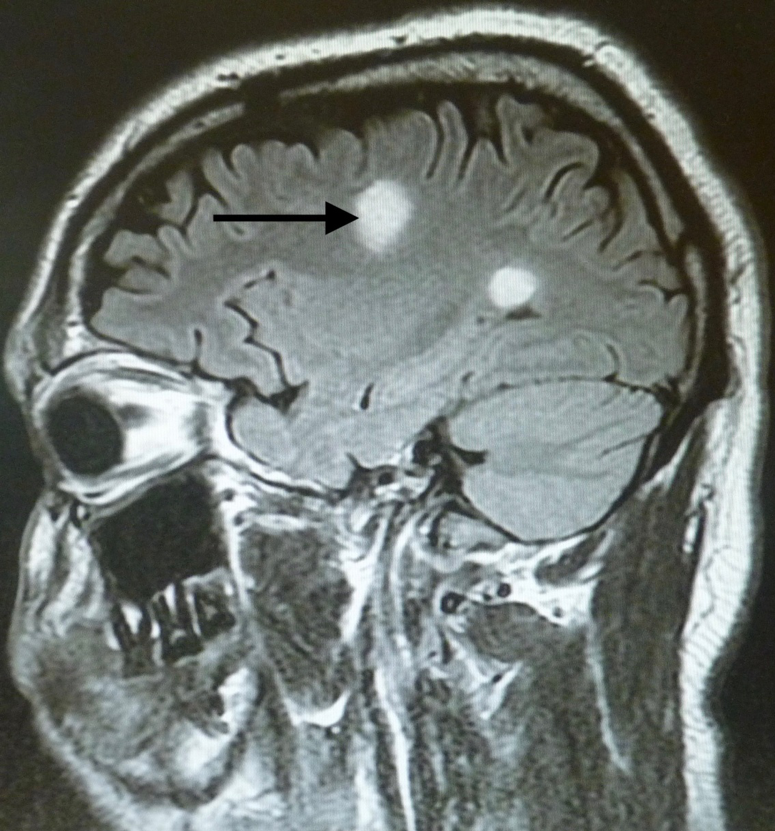

Magnetic resonance imaging (MRI) scans of the brain showed an abnormal area of increased signal intensity in the left centrum semiovale measuring approximately 1.8 cm, and another in the left periatrial region measuring approximately 1.2 cm (Figure 1). The lesion at the semiovale showed ring enhancement on one view, which prompted a differential diagnosis of neurocysticercosis (Figure 2).

Figure 1. Abnormal areas of increased signal intensity on fluid-attenuated inversion recovery (FLAIR) and T2-weighted imaging. The one in the left centrum semiovale measured approximately 1.8 cm, and the other measured approximately 1.2 cm.